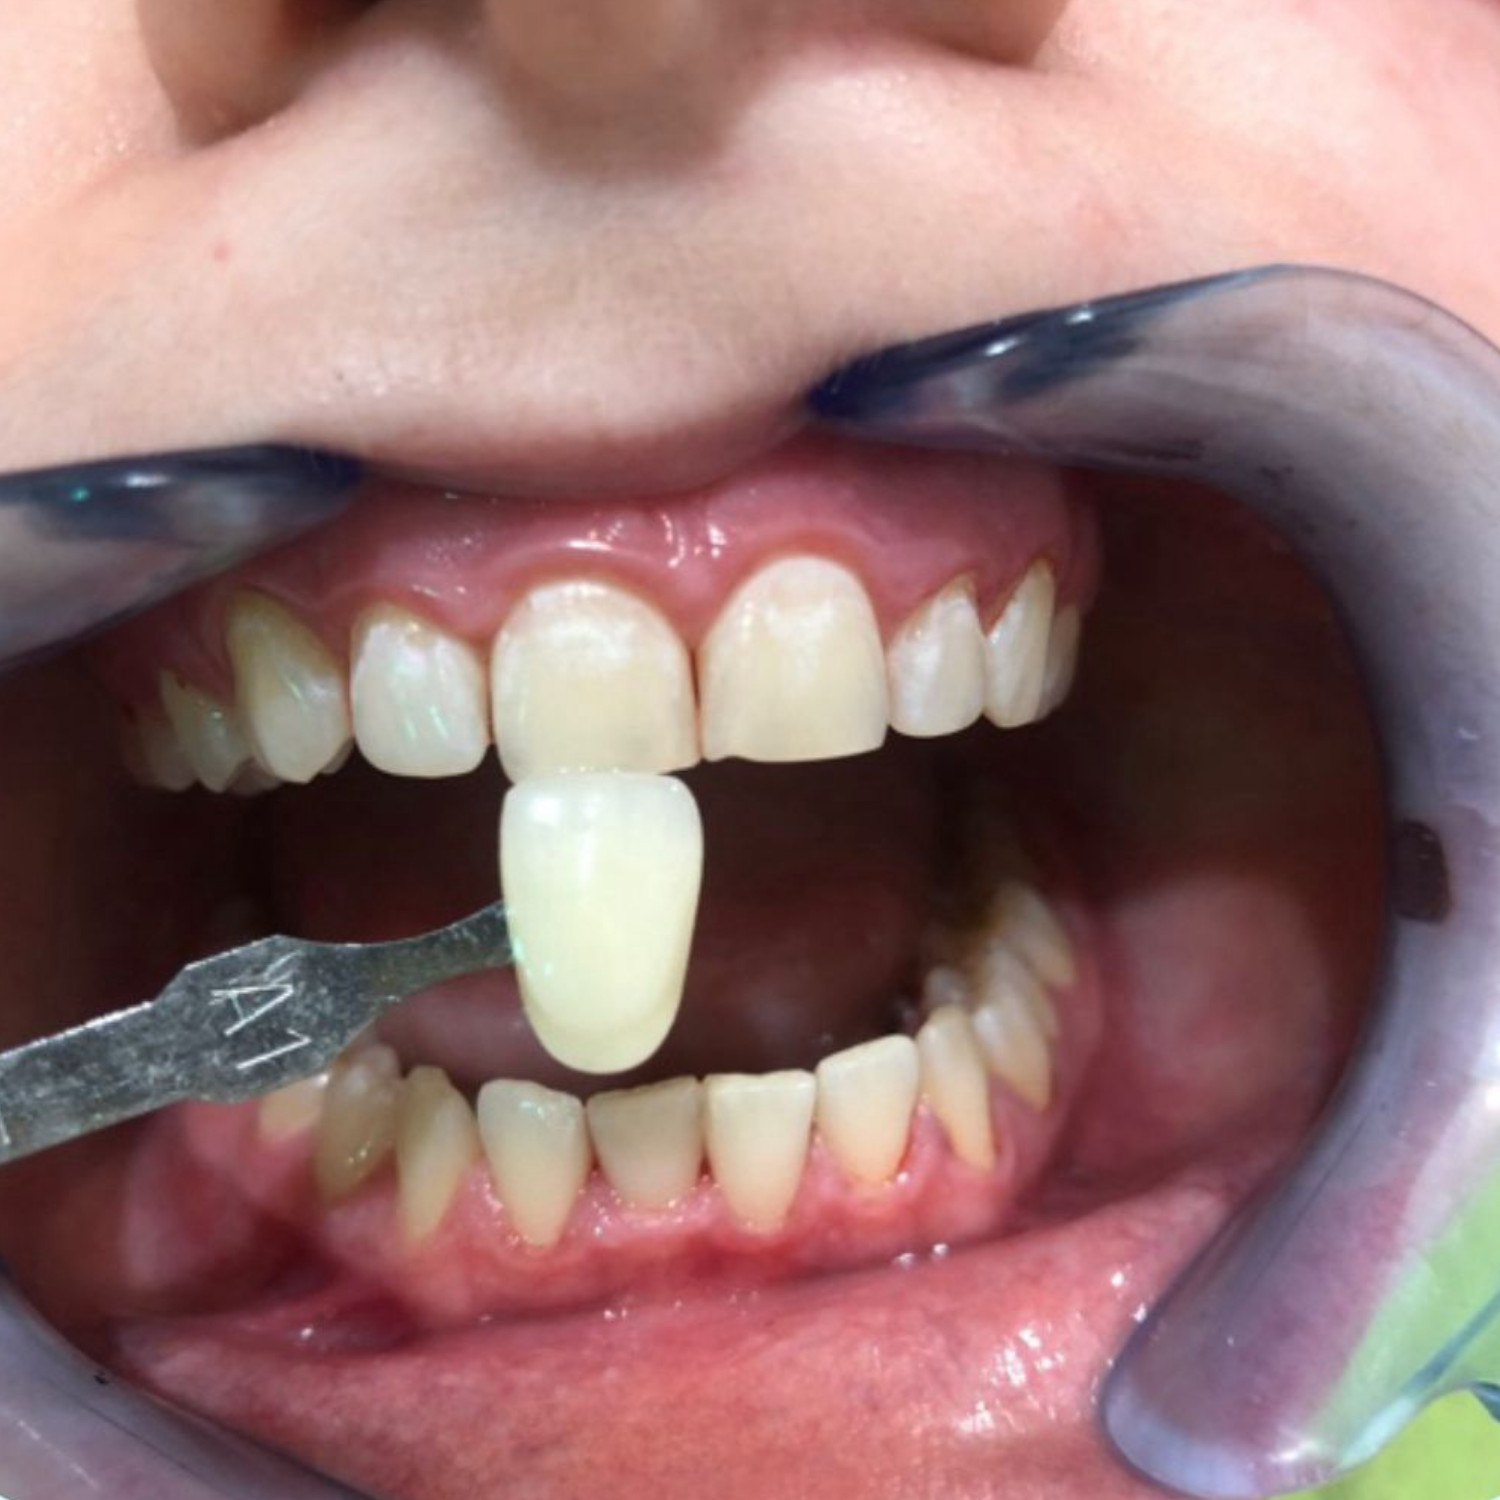

Il trattamento sbiancante medicale è un trattamento ad alta concentrazione di perossido di idrogeno in grado di produrre ottimi risultati in un’unica seduta, anche partendo da tonalità molto scure. ideale per affrontare le situazioni più difficili, come denti con colorazioni estremamente scure o affetti da discromie derivanti da terapie farmacologiche, oppure per tutte quelle situazioni in cui è richiesto un colore molto bianco per necessità di immagine (ad esempio i matrimoni) o di lavoro.